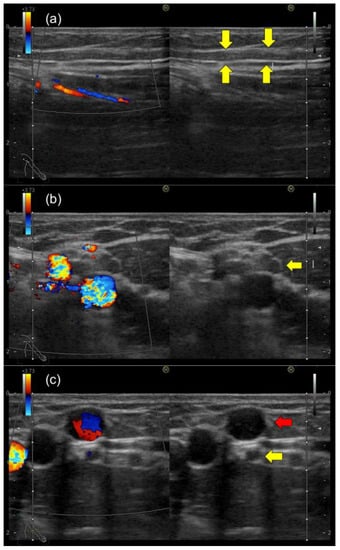

2. Case Report